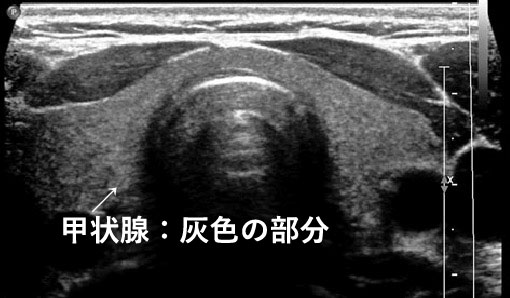

正常な甲状腺のエコー画像

甲状腺がんのエコー画像

甲状腺とは?

のどぼとけの下にある蝶のような形をした臓器です。

新陳代謝を促進し、脈拍数や体温を調節するホルモンを分泌します。